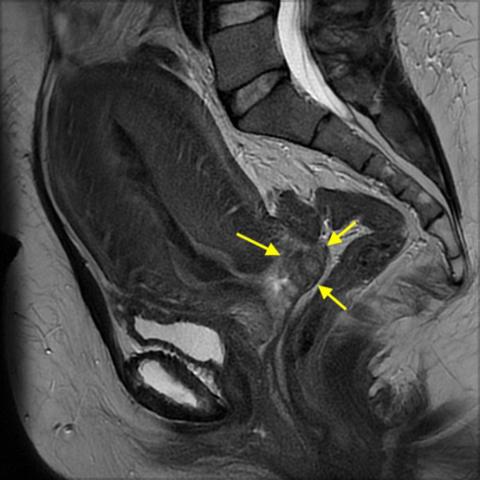

MR-skanningsbillede, der viser tumor i forreste portiolæbe (gule pile). Gengivet med patientens tilladelse.